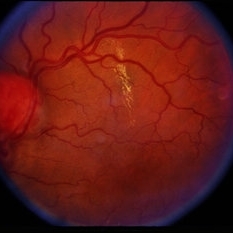

Retinal Capillary Hemangioblastoma

Feb 20 2015 by H. Michael Lambert, MD

Retinal capillary hemangioblastoma associated with Von Hippel-Lindau Disease. No history. Dilated tortuous vessel and hemorrhage is shown.

Condition/keywords: retinal capillary hemangioblastoma